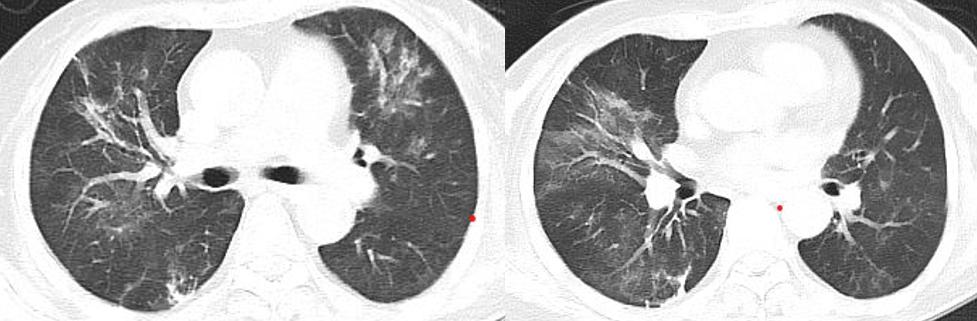

胸部CT示(12-18):两肺多发斑片絮状影,右中肺及两下肺实变,考虑感染可能。

治疗中患者的氧合指数仍然在快速下降,我们复查CT,显示大部分病变在进展。

图:胸部CT(12-24):两肺纹理增多,两肺门影增浓,两肺野内多发斑片影,较前2021-12-18部分稍有好转,部分稍明显。

图:胸部CT(12-31):两肺野内多发斑片影,较前好转。